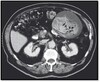

What pathology is seen here?

Pancreatitis ## Footnote Chronic: Calcifications, appear smaller

Pancreatic Cancer ## Footnote -In the head of the pancreas -Hypodense (dark compared to the rest of the pancreas) -Contrast image shown here (always look for contrast when identifying) -Gallbladder appearing larger (blocked duct causing things to back up)